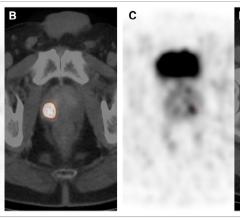

February 5, 2018 — Using nuclear medicine, German researchers have found a way to accurately differentiate cancerous ...